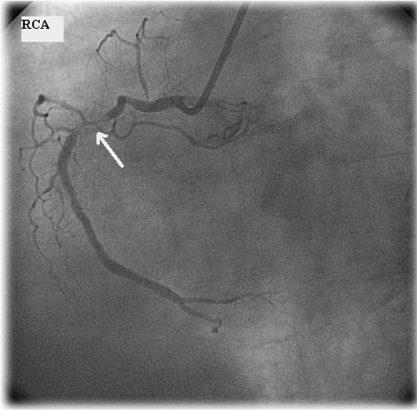

There were 34 ischemic segments in MPS and 46 in stress Echo among 493 segments of 29 patients. Both MPS and stress Echo pointed the same ischemic segments in 9 patients and tests were in agreement in 24 patients. However, only sixteen patients had angiography results (Table 2). The imaging results of the patients with angiography results were as follows; 6 patients with anterior, 6 patients with inferior, one patient with septum defect and three patient with normal perfusion were present also echo showed same regions hipokinesia in 9 patients and normal results in three scintigraphically normal patients. Angiography confirmed two test's results in 13/16 patients (Figure 1 represents a patient with similar results in both tests and confirmation result with angiography). Three patients with severe ischemia on MPS and stress Echo had slow flow pattern on angiography. The sensitivity, specificity, accuracy, negative, positive predictive values of the methods were 100%, 50%, 81%, 77%, and 100% for MPS and 90%, 60%, 81%, 77% and 90% for Echo respectively and are summarized in (Table 3) which shows very similar results for both tests. If we discard the patients with slow flow pattern results in angiography the sensitivity, specificity, accuracy, positive and negative predictive value of the MPS and Echo would be 67%, 43%, 69%, 60%, and 100% versus 100%, 71%, 85%, 75% and 100% respectively.

Figure 1a: Short axe, vertical and horizontal long axe and bull's eye images of MPS of a patient showing inferolateral wall ischemia whose stress Eco revealed inferior wall ischemia. View Figure 1a